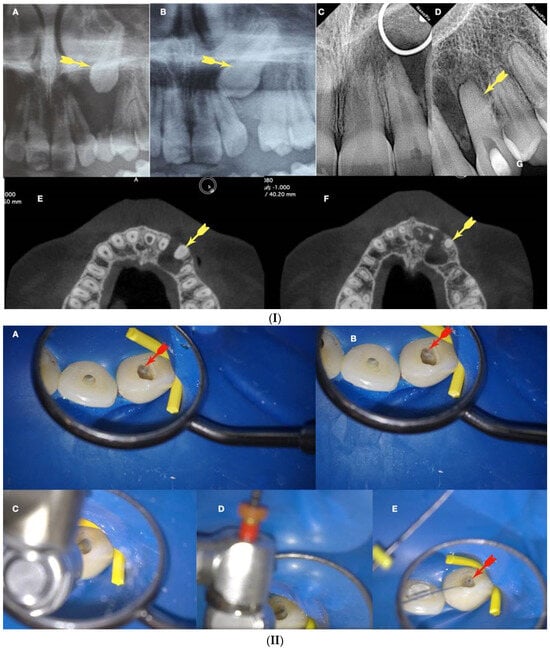

Figure 1.

(A) Periapical radiograph of an abraded calcified mandibular incisor with no visible canal lumen. (B) Three-dimensional micro-ct reconstruction of the same calcified mandibular incisor that was extracted for prosthetic reasons. The micro-ct reveals a patent canal. (C) Apical root canal anatomy of the calcified canal lumen sectioned, revealing canal bifurcation and apical anastomosis (Skyscan 1172 micro-CT scanning device, Bruker MicroCT, Belgium) (images courtesy of Dr. Alexey Volokitin, city of Dnepr, Ukraine).

Figure 2.

Axial micro-ct slices of the calcified mandibular incisor of Figure 1 reveal the cross-sectional root canal dimensions along the root. The crown of the tooth is completely blocked, and the canal is visible starting at the level of the CEJ. The root canal dimensions are constricted along the coronal part of the root, becoming wider in the middle, followed by an apical splitting into two canals. Calcified cases usually present an inverted taper (Skyscan 1172 micro-CT scanning device, Bruker MicroCT, Belgium) (images courtesy of Dr. Alexey Volokitin, city of Dnepr, Ukraine).